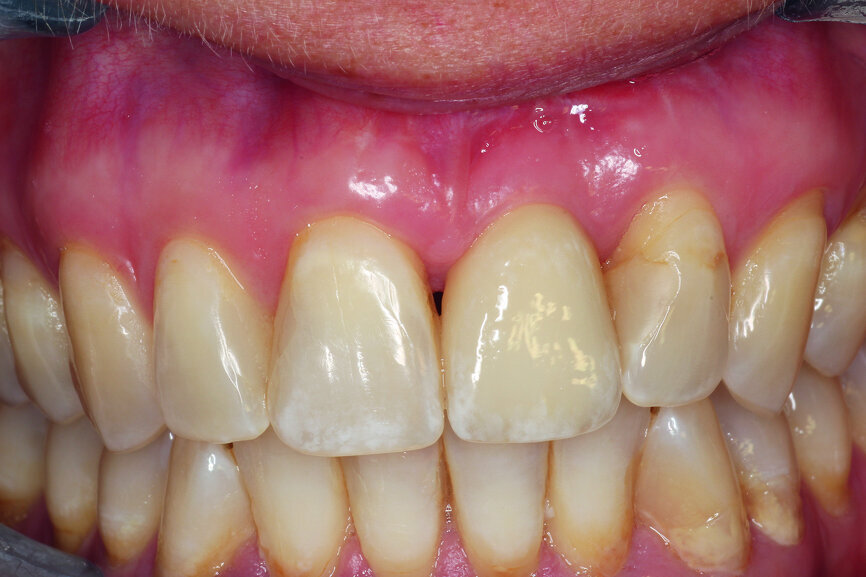

A 40-year-old female patient presented to our dental surgery with an irreparable tooth #21 (Fig. 1). The periapical radiograph revealed an approximately 7 mm periapical translucency with widening of the periodontal ligament in the upper third of the root (Fig. 2). Owing to the clinical conditions (high smile line and good oral hygiene), we decided to use a two-piece ceramic implant, ZERAMEX XT (Dentalpoint).

Fig. 1: Initial clinical situation.